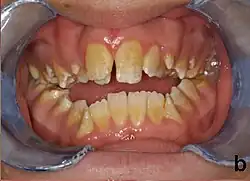

Amelogenesis imperfecta, hypoplastic type. Note the association of pitted enamel and open bite.